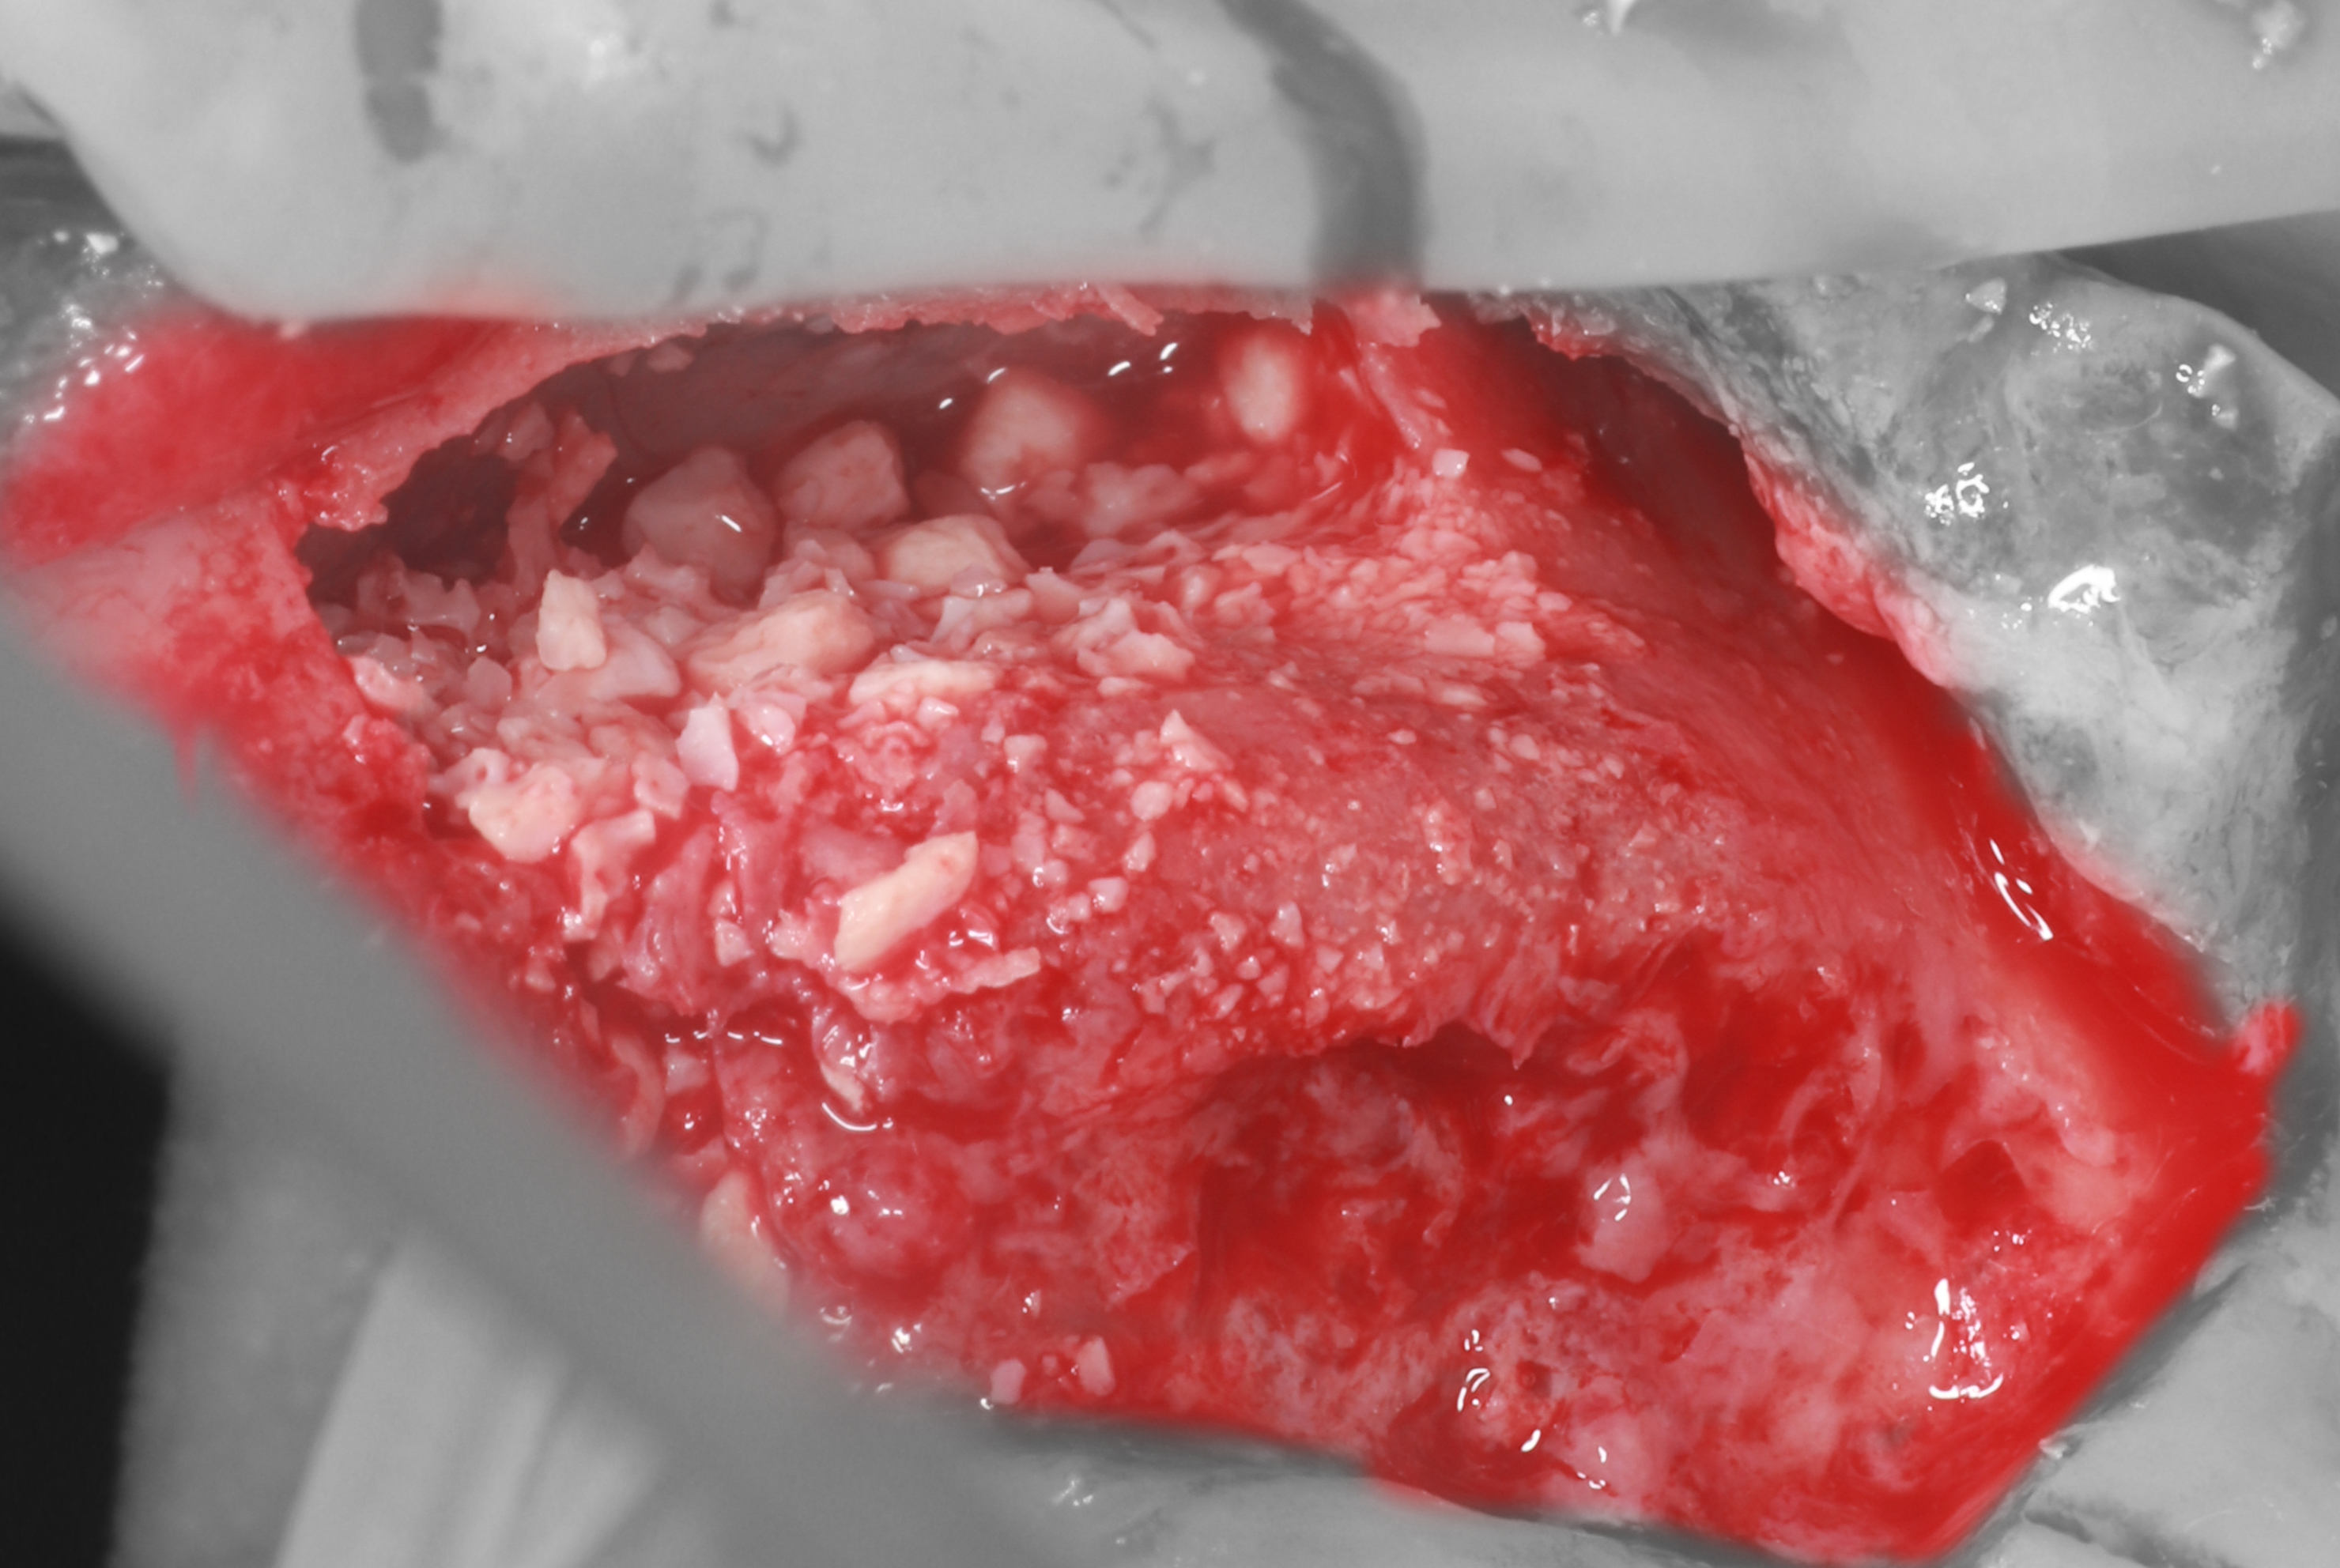

6) Инсулиновый шприц, заполненный смесью ксеногенного костнозамещающего материала и аутогенной стружки.

7) С помощью шприца материал внесен в субантральное пространство.

8) Более 1,5гр. графта помещены к небной стенке, но полость все ещё остается незаполненной до конца.

9) Было принято решение вестибулярную часть полости заполнить ксеногенным коллагеновым материалом.

10) Агументат изолирован от вестибулярного лоскута с помощью костного блока (с вестибулярной стороны) и коллагеновой мембраной (с крестальной стороны).